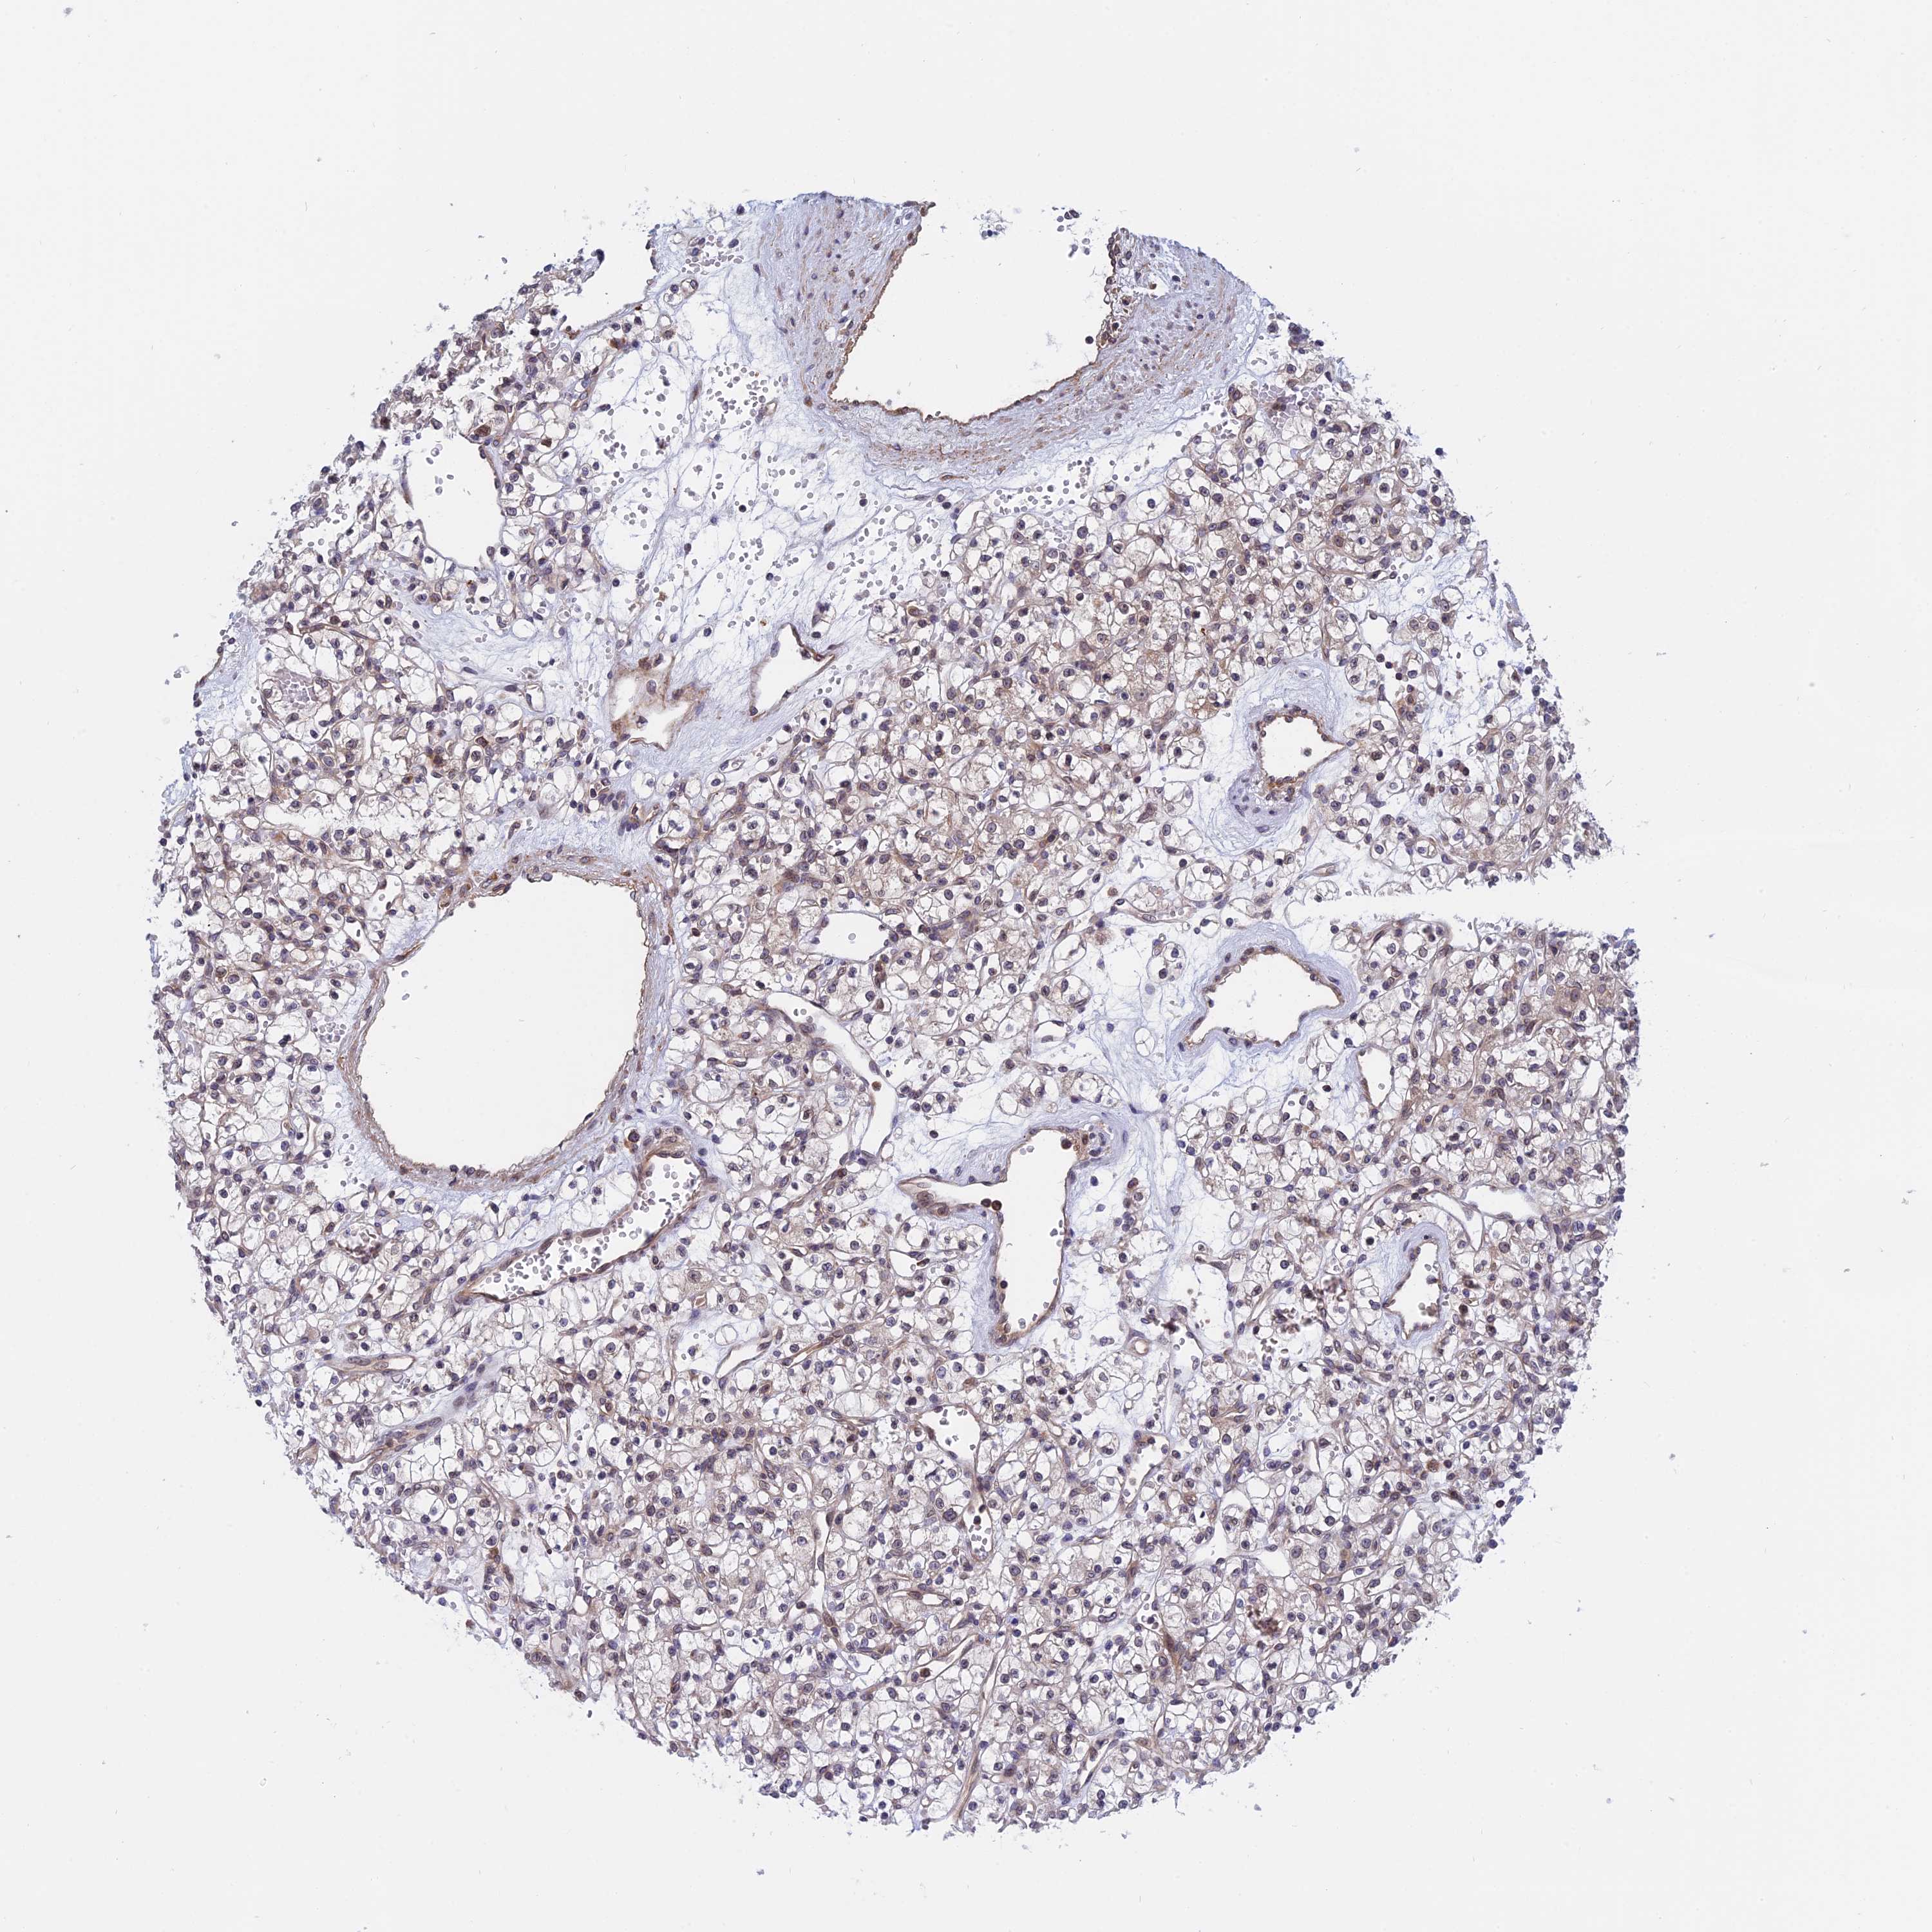

TCGA RNA samplesi

RNA-seq data is reported as average FPKM (number Fragments Per Kilobase of exon per Million reads), generated by the The Cancer Genome Atlas (TCGA) .

Normal distribution across the dataset is visualized with box plots, shown as median and 25th and 75th percentiles. Points are displayed as outliers if they are above or below 1.5 times the interquartile range. FPKM values of the individual samples are presented next to the box plot.

Average pTPM 35.8